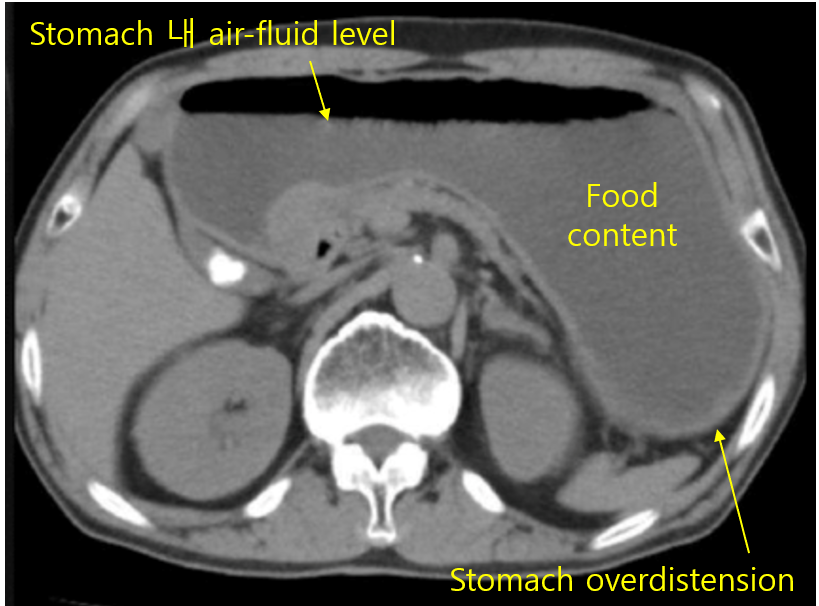

(2) CT: Pyloric obstruction, stomach distension

폐쇄 | • 구토, 탈수, 전해질 불균형 • 치료: 보존적 치료(코위관 감압) → 풍선 확장술, 수술적 연결술 |